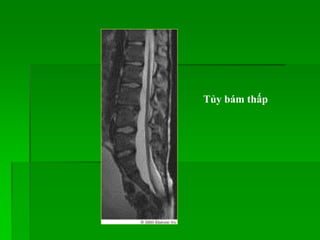

Tủy bám thấp

Tủy tận cùng

dưới thân

sống L2

(bình thường

ngang mức

L1-2).